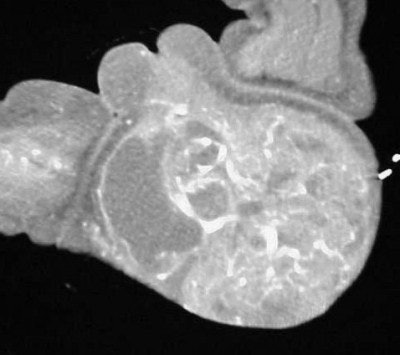

In figure TC 3 we can see a large soft-tissue mass measuring approximately 9 cm wide by 6 cm in AP diameter, and 14 cm in height. It contains both fluid and semi-solid components of soft tissue as well as assorted calcifications. The mass appears to terminate (Figure TC 4) just above the level of the uterus (arrow).

The images (Figures TC 5 and TC 6) show, respectively, a sagittal and coronal MPR of the axial images, demonstrating the size and volume of the structure.